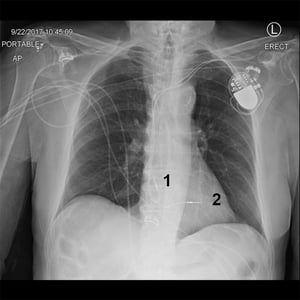

ペースメーカーを装着している患者の胸部X線

このX線写真には,左上胸部にペースメーカーがあり,右房(1)および右室(2)にリードが留置されている患者が写っている。

© 2017 Elliot K.Fishman, MD.